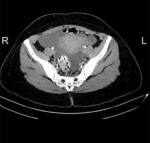

Diagnostic assessment: laboratory investigations revealed a microcytic anemia (hemoglobin count of 9.9g/dl and mean corpuscular hemoglobin of 67 Fl). Her Ca 125 was 10 U/ml, and other tumor markers were negative. She had normal renal and liver function. An ultrasound scan (USS) of the pelvis showed multiple pelvic cysts, a right adnexal cyst measured 60 mm x 43 mm, and a left adnexal cyst measuring 52 mm x 31 mm was noted. Risk of malignancy index was 10. Computed Tomography (CT) images also showed the pelvic cysts around the rectum, sigmoid colon, and uterus (Figure 1, Figure 2, Figure 3)

Figure 1: axial computed tomography image of the pelvis showing pelvic cysts